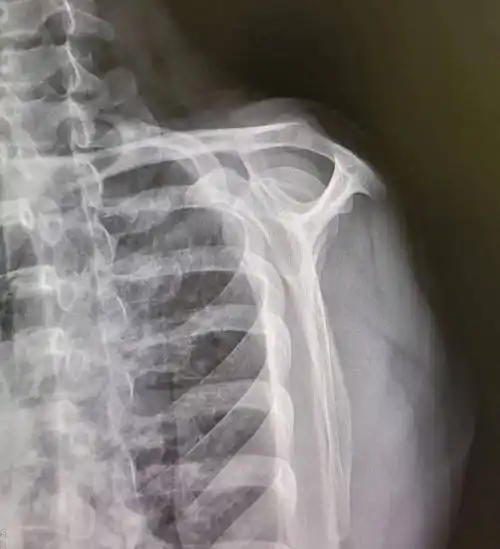

一张肩关节平片

正常距离为10~15mm,狭窄为小于10mm,严重肩袖损伤为小于5mm.